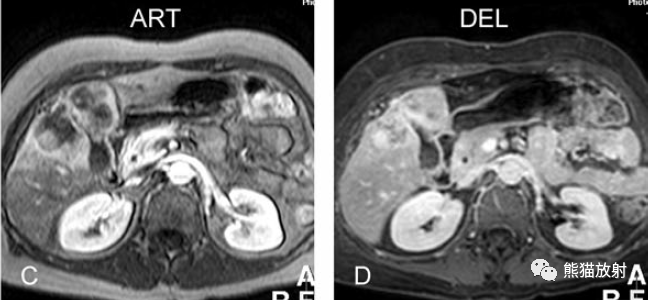

膽囊癌。A~D圖:上方層面,表現(xiàn)如上所述,形成腫物侵及肝臟。E、F圖:下方層面示膽囊壁不規(guī)則增厚,明顯不均質(zhì)強(qiáng)化。

膽囊壁增厚(并肝硬化、門(mén)脈高壓、腹水)。T2WI顯示膽囊壁因水腫而光滑均勻增厚,增強(qiáng)延遲期顯示強(qiáng)化的膽囊壁(內(nèi)外兩層:粘膜層和漿膜層),薄而清晰光滑。